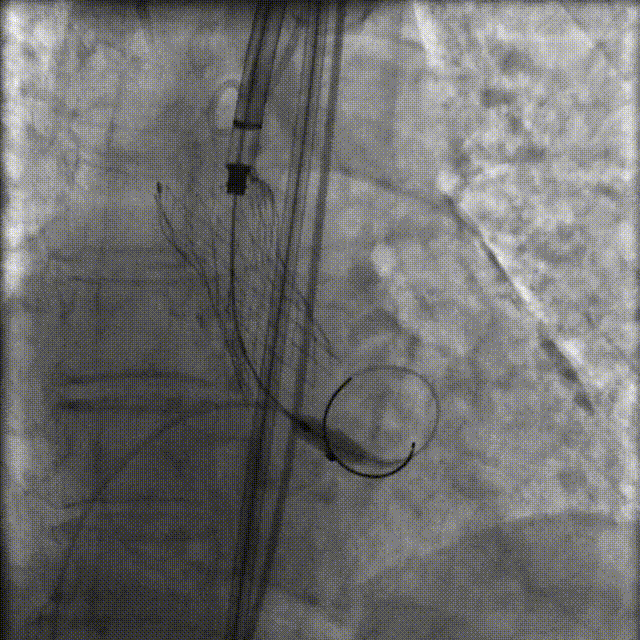

成功跨越主动脉瓣后依次使用18mm和20mm球囊预扩张

图片

球囊扩张